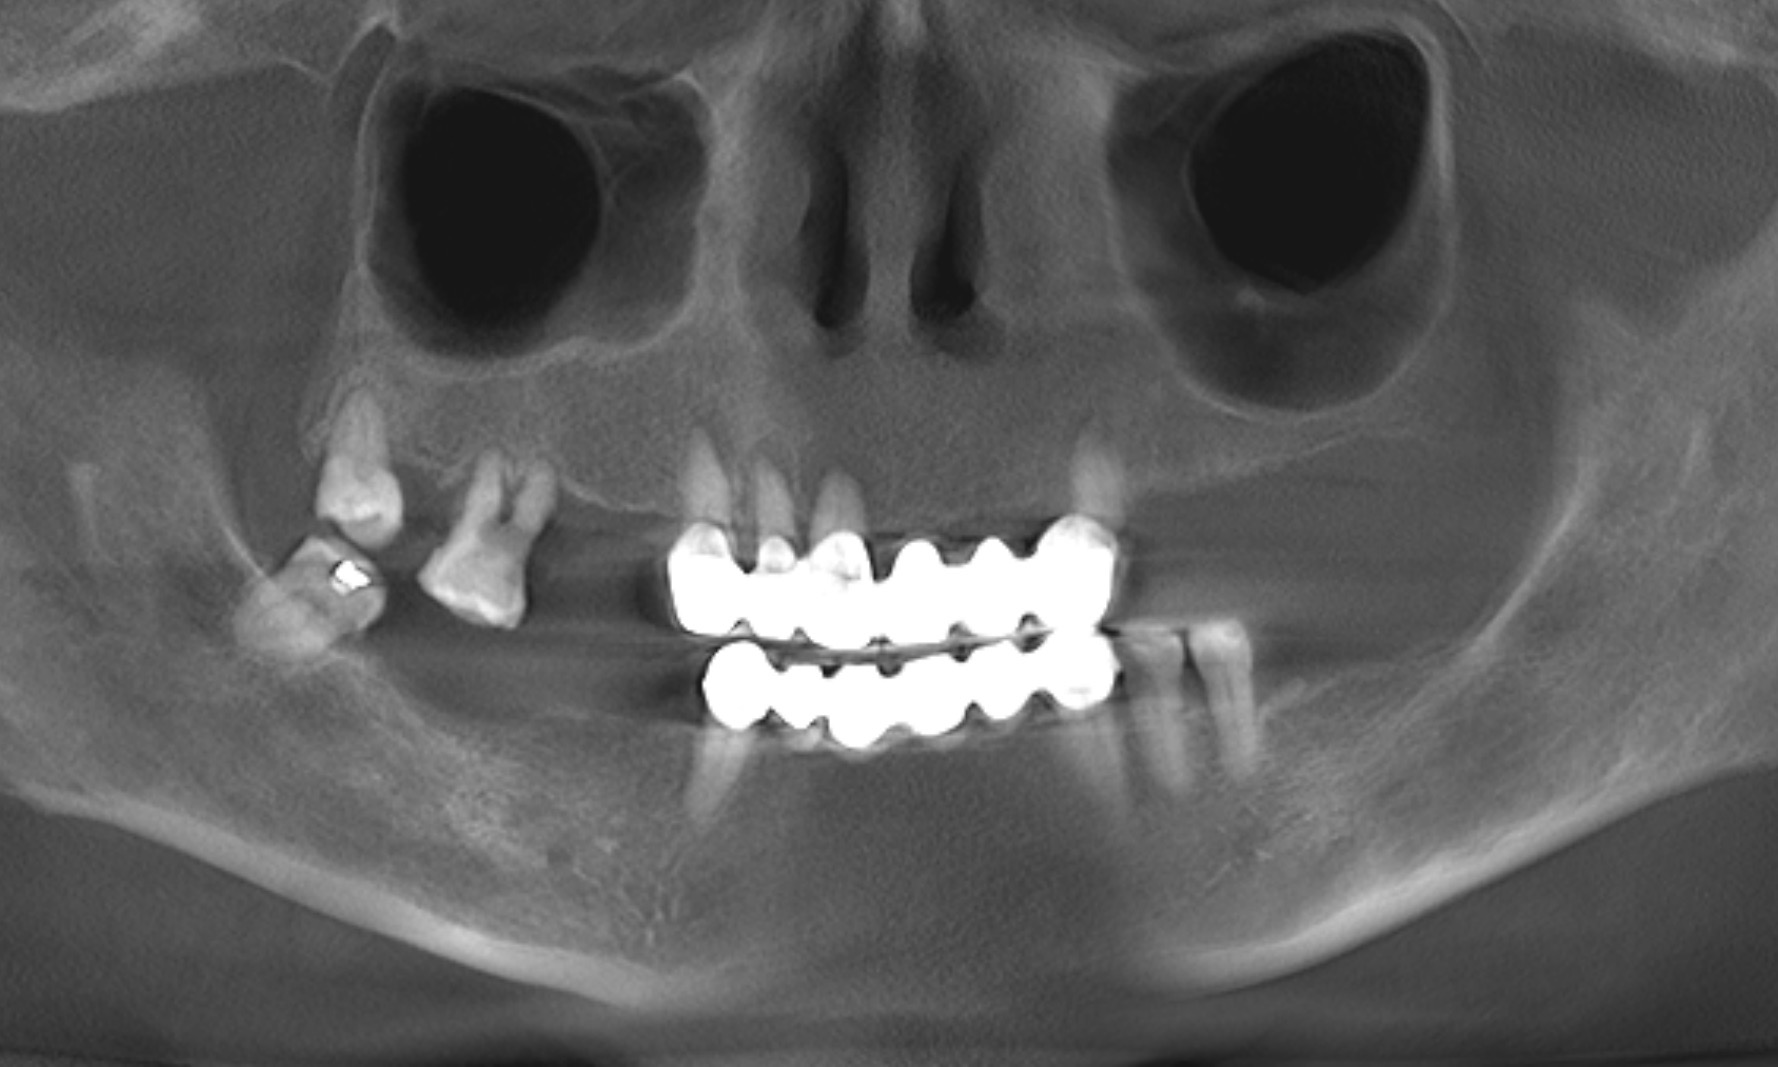

The extra-oral examination showed a low smile line, and the intra-oral examination found a removable bridge from tooth #13 to tooth #23 that was poorly adapted and showed signs of deterioration. The maxillary teeth, with the exception of tooth #18, were mobile. Generalised gingival inflammation, bleeding on probing and dental caries were also present (Fig. 1). The radiographic examination exposed severe bone loss in the posterior of the maxillary left quadrant, as well as caries and apical lesions on maxillary teeth (Fig. 2).

After two years, clinical and radiographic control of the rehabilitation was carried out (Figs. 14 & 15). The soft and hard tissue surrounding the implant exhibited favourable conditions. Furthermore, the patient had gained a deeper understanding of her oral health and acquired knowledge on how to maintain proper oral care.